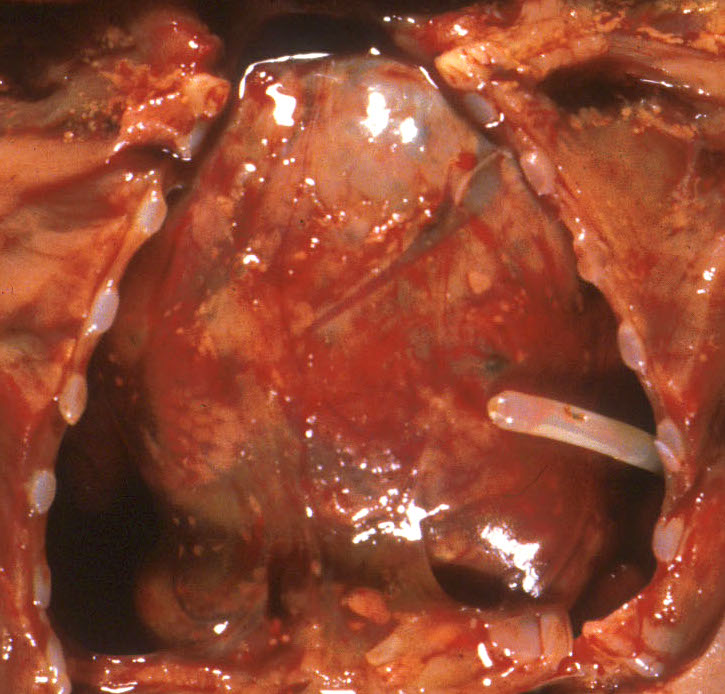

The other mechanism producing pulmonary hypoplasia is a mirror image of oligohydramnios in that external forces within the chest cause restricted lung growth by opposing the lung expansion from the amniotic fluid pressure. These forces may include an intrathoracic mass effect from tumor or fluid (Fig 3a, b)

, or restriction of the thoracic volume by an osteochondrodystrophy (Fig 4a, b).